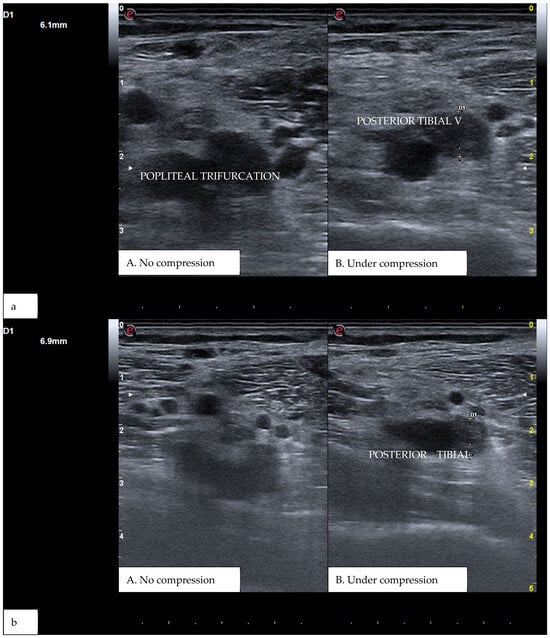

Figure 3. (a) A real example of DVT at the level of the right popliteal trifurcation with posterior tibial vein involvement. (b) Represents the same patient at a more distal section. D1 shows the residual diameter of the non-compressible vein (i.e., the maximum diameter of the relative venous thrombus).

CUS is a diagnostic technique primarily designed to find DVT by checking the veins’ compressibility with the principle that healthy veins are normally compressible and would collapse under the pressure of the ultrasonographic probe. In the case of the presence of a venous thrombus, the vessel would not be able to collapse under such pressure [8,9]. Linear high-frequency transducers are generally used for CUS as they best visualize leg veins [10]. The ultrasound machine settings must be adjusted carefully in order to limit possible operator-related bias. Important elements to be considered in this setting include gain, focus, and time-gain compensation. Gain adjustment regulates image brightness, focus optimization sharpens the image to the desired depth, and time-gain compensation enhances the visibility of subtle echoes, ensuring uniform image quality [10,11]. The transducer partially compresses the vein, which creates an echogenic response. In normal veins, this technique should fully compress the lumen [9]. However, with thrombosis present, the vein does not collapse enough, which causes a non-continuous echogenic line [12]. While the femoral veins are usually well identified in the groin and thigh areas, to facilitate better visibility of the popliteal veins, the patient may lie in a supine position with the leg slightly abducted to relax the muscles or, alternatively, in a prone position [9]. Real-time B-mode and Doppler imaging are both valuable tools in this process. B-mode imaging can find incomplete vein collapse during compression [13,14]. Doppler imaging can show the thrombus or find a complete lack of flow in the lumen [9]. As such, CUS for DVT diagnosis involves evaluating direct signs like the presence of a non-compressible echogenic line suggesting a thrombus, as well as indirect signs like changes in vein compressibility and thrombus echogenicity [6,7]. In addition, evaluation of flow patterns and flow response during augmentation maneuvers may refine the diagnostic examination, although their implementation requires more advanced training and skills than simple CUS [7]. Clinicians should assess a spectrum of veins, including the external iliac, common femoral, superficial and deep femoral, popliteal, tibial, peroneal, gastrocnemial, and soleal veins, as well as the junctions with the great and small saphenous veins, representing the superficial systems [15]. Challenges exist in visualizing the iliac veins, especially in obese patients, yet phasic flow in the femoral veins can be indicative of DVT status, particularly for excluding iliac vein thromboses [16]. This comprehensive approach is standard in differentiating healthy veins, which should collapse and enlarge with augmentation maneuvers, from those with thrombosis, which show impaired response to pressure and flow changes [12,17]. Figure 1, Figure 2, Figure 3 and Figure 4 show real examples of DVT affecting different sites of the lower limb deep venous system, diagnosed through a CUS modality.